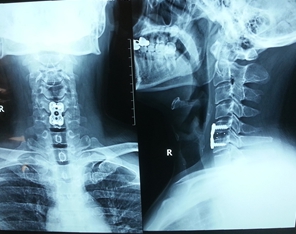

2.颈前路减压植骨钛质钢板内固定。

3.颈椎、腰椎椎间融合器。

图2.颈椎病间盘摘除、CAGE植入、钢板内固定术后